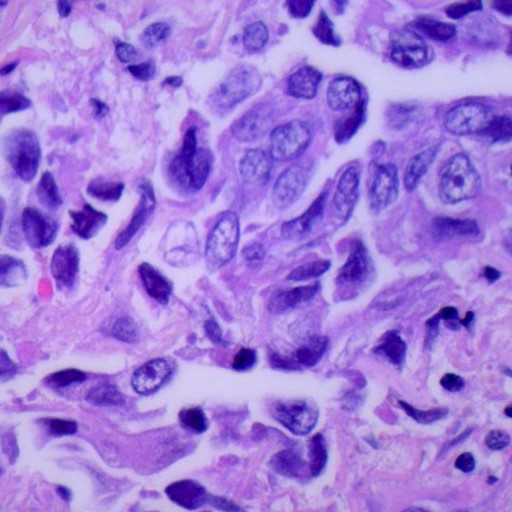

CancerExpert

Comprehensive detection for 26 cancer types using multi-modal imaging and biomarker analysis.

Multi-Cancer Early Detection

Revolutionary system combining radiological imaging, pathology, and molecular data for early cancer detection across 26 types.